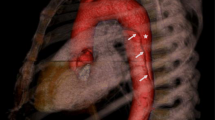

An AAA can be defined as a permanent localised dilatation of the abdominal aorta above a diameter of 3.0cm [69]. Like in TAAD, the aortic wall in AAAs exhibits destruction of elastin/collagen structures and a loss of SMCs, but it also shows significant inflammation and neovascularisation [70]. Although there is some overlap between the two diseases—up to 28% of those with an AAA also have a TAA [71]—TAA and AAA have been shown to segregate independently through family lineages [69], i.e. a family history of TAA has a minimal effect on the risk for developing AAA and vice versa. This could be because the two vessel segments have different embryological origin: abdominal SMCs are derived from mesoderm, while thoracic SMCs are derived from neural crest cells [72]. Furthermore, unlike TAAs, it is not yet possible using variants alone to categorise AAAs into distinct groups with different prognoses. A visual comparison of the two types of aortic aneurysm is shown in Fig. 2.

Knowing which genetic variant is carried by a patient can affect management. Many variants lead to dissections under the 5.0–5.5 cm diameter range that is normally used as the threshold for surgery, so early intervention (usually curative) is warranted (Fig. 1). Furthermore, some variants are associated with a more rapidly progressive disease phenotype, as tends to be the case with familial-variant patients who present at an earlier age than those with sporadic-variants (58.2 vs 65.7) and have aneurysms that grow at faster rates (0.21 vs 0.16 cm/year) [17]. These factors may be relevant when deciding the frequency of follow-up scans, and the timing of the operation as the surgical threshold may be met sooner. Standard beta-blocker therapy to slow growth (widely practiced, but questionably effective) and avoidance of isometric exercises and contact sports, which are known triggers of dissection, would continue to be of use. A summary of different proposed surgical guidelines is shown in Fig. 1.

Surgical guidelines for patients carrying variants in specific genes involved in the development of TAAD based on current expert opinion. Those in red are the most recently discovered [9••]